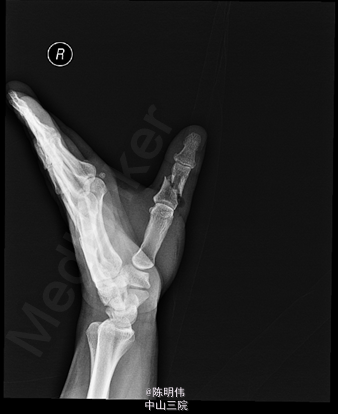

右拇指正侧位示:右拇指近节指骨中段可见斜行骨折线影,骨折两端明显成角及错位,其周边软组织肿胀;